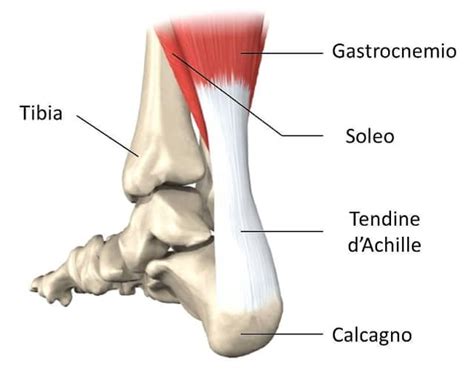

Anatomia del Tallone e del Tendine d'Achille

Il tallone è l'estremità posteriore del piede, la cui struttura anatomica è costituita principalmente dal calcagno, l'osso più voluminoso del tarso. Ad esso è collegata la fascia plantare e, sulla parte posteriore, si inserisce il tendine d'Achille. Questo tendine, il più grande e resistente del corpo umano, collega i muscoli del polpaccio al calcagno, permettendo movimenti essenziali come camminare, correre e saltare.

La superficie posteriore del calcagno è divisa in tre parti: superiore, media e inferiore. La parte superiore è liscia e triangolare, situata sopra la borsa retrocalcaneare. La parte media, ruvida, ospita la borsa retrocalcaneare e l'inserzione del tendine d'Achille. La parte inferiore sostiene il peso del corpo.

Il tendine d'Achille, con una lunghezza che varia da 10 a 12 centimetri, è una struttura fondamentale per la propulsione del corpo. Nonostante la sua resistenza, è considerato uno dei punti deboli del corpo umano, specialmente per gli sportivi.